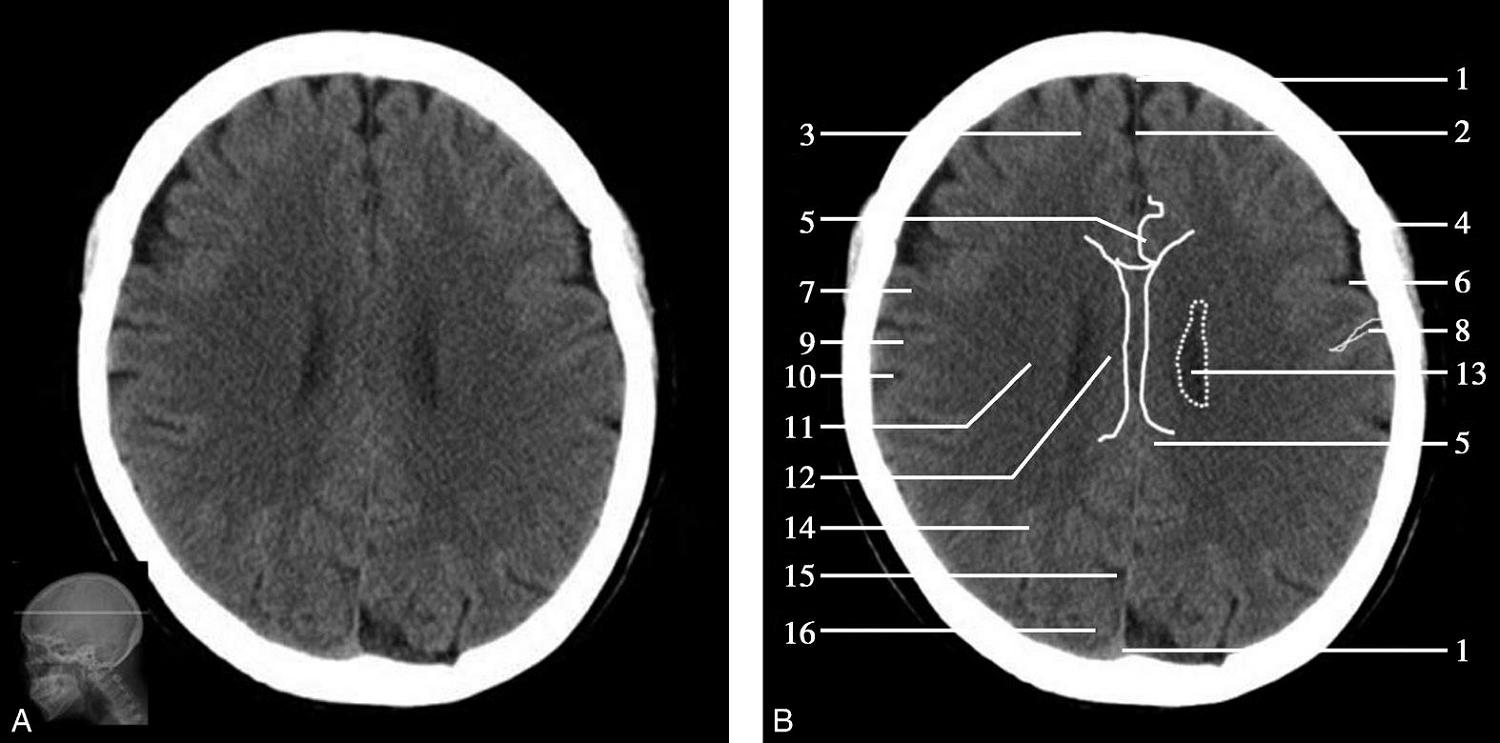

重要结构:卵圆孔、棘孔、破裂孔、斜坡、颞骨岩部、颈静脉孔(图1-2-1、图1-2-2)。

图1-2-1 颅底层面

A.横断面;B.横断面标注

1.晶状体;2.筛窦;3.颞肌;4.中颅窝底;5.外耳道;6.延髓;7.乙状窦;8.小脑半球;9.眼球;10.眼眶;11.上颌窦;12.蝶窦;13.乳突;14.耳郭;15.小脑蚓部;16.枕内隆凸

图1-2-2 颅底层面(骨窗)

1.鼻骨;2.筛窦纸板;3.颧骨眶突;4.翼腭窝;5.蝶骨大翼;6.卵圆孔;7.破裂孔;8.颞骨颧突;9.棘孔;10.斜坡;11.颞骨岩部;12.乳突;13.颈静脉孔;14.枕乳突缝;15.枕骨;16.枕内隆凸

层面前部呈开口向前的“V”字形,正中为鼻中隔,向两侧依次为筛窦和眼眶,眼眶内前部为眼球,后部为眶脂体。翼腭窝位于眼眶后部,窝内含有脂肪并有上颌神经通过。层面中部为蝶骨体,蝶骨体中部可见含气蝶窦,蝶窦后方为枕骨基底部,两者呈前后关系,其上面构成斜坡。蝶窦两侧为蝶骨大翼,其后外侧缘处由前向后可见卵圆孔和棘孔,分别有下颌神经和脑膜中动脉通过。斜坡外侧、岩骨尖前方为破裂孔。蝶骨大翼与眶外侧壁的颧骨借颧弓相连,颧弓和蝶骨大翼之间有咬肌及颞肌。层面中部外侧为外耳道。颞骨岩部呈“八”字形,相互之间借破裂孔软骨、蝶岩软骨结合和岩枕软骨结合连接。岩部后外侧的乳突部内可见乳突小房,乳突部与枕骨相接。岩骨后部可见颈静脉孔,内有颈内静脉、舌咽神经、迷走神经和副神经通过。层面后部为颅后窝,其内可见延髓,延髓前方为延髓前池,内有椎动脉,后外侧为小脑半球下部,后方为第四脑室、小脑扁桃体及小脑蚓部。

破裂孔、卵圆孔、棘孔及斜坡等均为重要的解剖结构,临床常见疾病如鼻咽癌常侵犯上述结构(图1-2-3)。颈静脉孔区较常见的肿瘤为颈静脉球瘤,常伴有颈静脉孔及其邻近骨质的破坏(图1-2-4)。